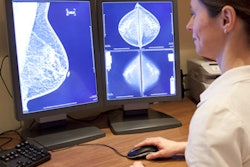

Roger Blanks, PhD, from the University of Oxford.The U.K. National Health Service Breast Screening Programme (NHSBSP) was established in 1987. Starting in 2008, digital mammography began to replace film-screen mammography, and by 2011, 80% of the program's sites had at least one digital mammography device. By 2014, 95% of the program's sites were fully digital.

Blanks and colleagues sought to evaluate the effect of digital versus film-screen mammography on cancer detection using data from the 80 facilities of the NHSBSP. The study included 11.3 million screening exams in women between the ages of 45 and 70. Of these, 2.3 million were routine first screening exams in women ages 45 to 52, and 9 million were subsequent screening exams in women ages 53 to 70. Among all of the exams, 86,443 cancers were identified, for a rate of 7.7 per 1,000 women screened.